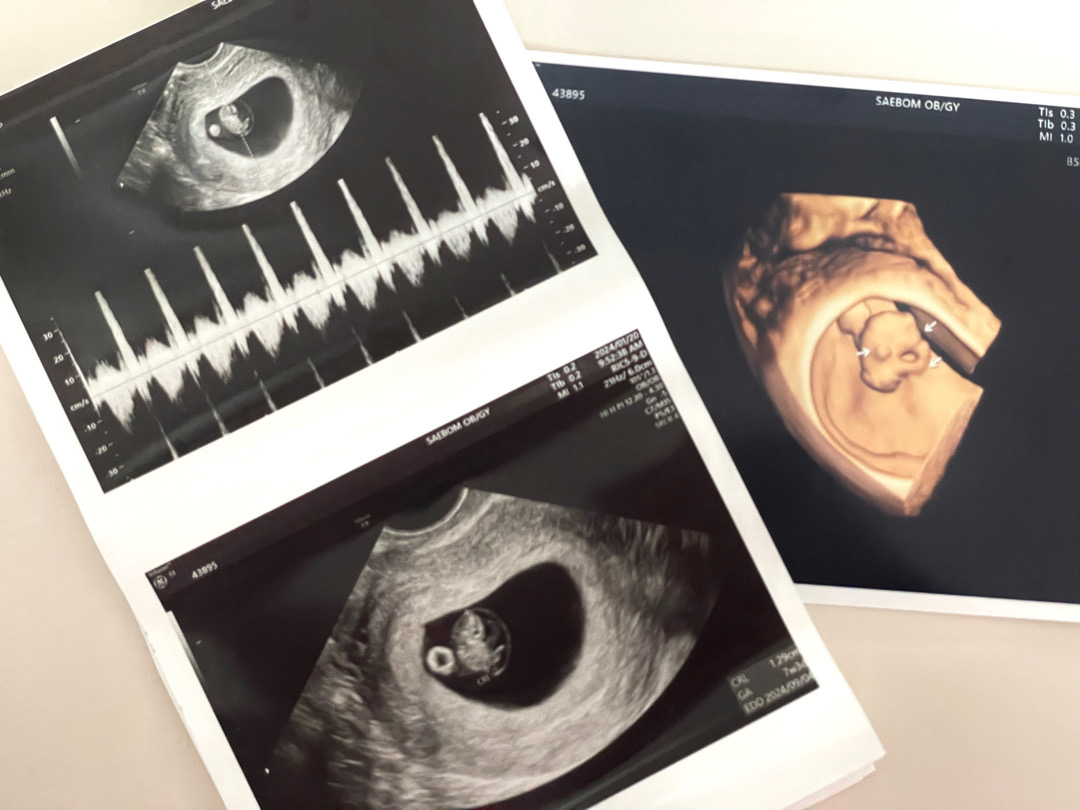

7주 3일 초음파

에일리언 같다고 생각했는데 팔도 나오고 있고 제법 눈사람 같은 모습이라 넘 싱기했어요ㅠㅠ 7주 3일 1.27cm! 눈 위치? 도 생긴것 같아 귀여워보이기까지.. 심장소리 들었을때 찡한 마음은 글로 표현하기 어렵네요 신랑이랑 싸우고(내탓) 홧김에 혼자 갔는데 ㅋㅋㅋ 혼자 먼저 들어서 미안했어요.. 다른 분들 처음 초음파 보고도 귀엽다고 하시는거 보고 내가 모성애가 부족한가 싶었는데, 이번에 다녀온 뒤로 자꾸 초음파 사진 보고 있는 나를 발견합니당😭😭😭 별일 아닌거에 자꾸 오열하게 되는데 호르몬 탓이겠죠 ㅋㅋㅋ...진상 ㅠㅠ 다들 건강하게 품고 낳길 바랍니다 🐉🫶